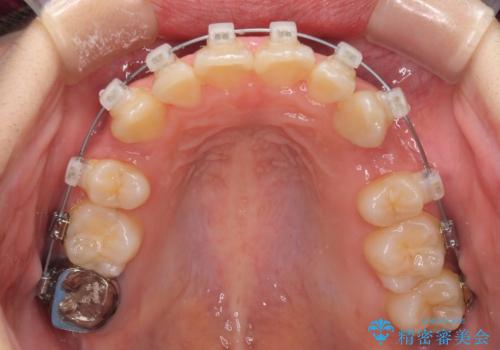

- 矯正装置

- クリアブラケット

- 治療期間

- 2年2ヶ月